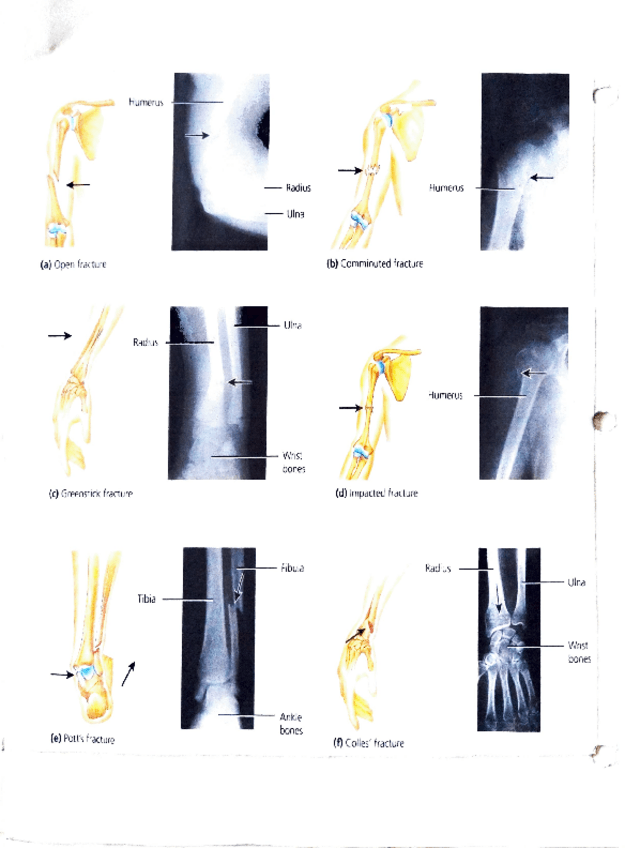

Apuntes - sistema-Esqueletico.pdf